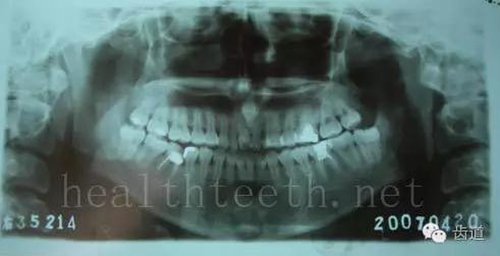

3、多生牙

病例2

50.jpg

51.jpg